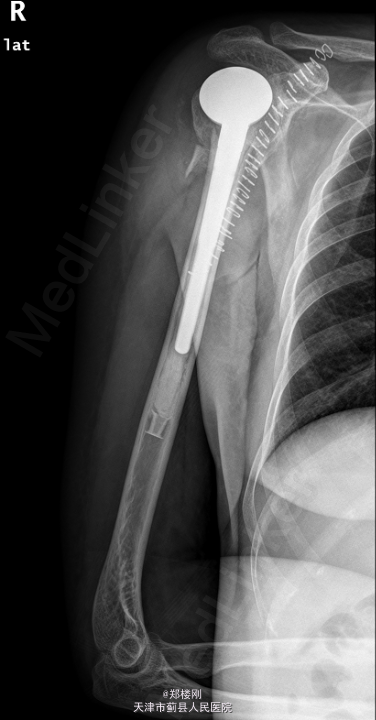

右肱骨近端骨折 全麻下行右半肩关节置换术

右上肢切口处敷料包扎固定妥,切口对合良好,切缘干燥,无明显红肿渗出,无明显感染征象,末梢手指活动、血循、感觉可。